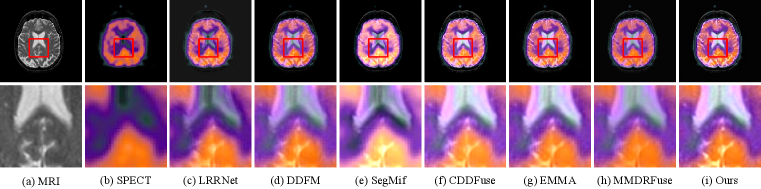

For MIF, we show the qualitative comparison in Fig. 10, 11 and 12. Our method fully integrates the detailed information of MRI images and the functional information of the other images. As shown in Fig. 10, our method clearly demonstrates the detailed information of the MRI images. As shown in Fig. 11 and 12, our method not only preserves the color information but also achieves higher contrast. This makes it much easier to observe the images for better medical diagnosis.

Refer to caption

Figure 10: Comparison of fusion results on the MRI-CT Harvard Medical dataset. The second row shows the enlarged regions in the first row.

Figure 11: Comparison of fusion results on the MRI-PET Harvard Medical dataset. The second row shows the enlarged regions in the first row.

Figure 12: Comparison of fusion results on the MRI-SPECT Harvard Medical dataset. The second row shows the enlarged regions in the first row.